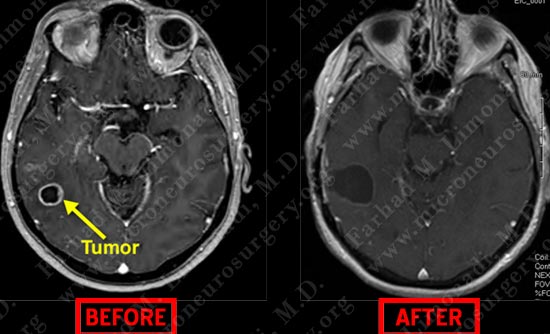

Post-op Imaging

Post operative MRI shows complete resection of tumor with appropriate margin.